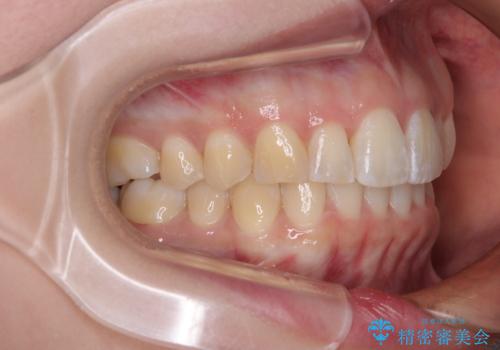

前歯の形が台形であり、歯列が整ったところでブラックトライアングルが目立つ仕上がりとなったため、IPR(歯と歯の間を削る処置)によって歯の形態を修正し、隙間の目立たない歯列に仕上げることができました。